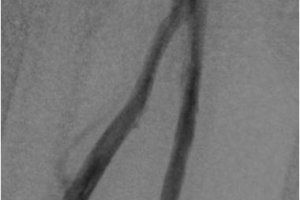

Посттромбофлебитическая болезнь (ПТФБ) развивается у 40-60 % пациентов после перенесенного тромбоза глубоких вен. ПТФБ является одной из разновидностей хронических заболеваний вен нижних конечностей и приводит к трофическим нарушениям. В центре сосудистой хирургии им. Т.Топпера активно занимаются реконструктивной хирургией вен. В настоящее время накоплен большей опыт лечения пациентов с посттромбофлебитической болезнью. Прежде всего это баллонная ангиопластика вен, которая по необходимости может быть дополнена стентированием. На базе нашей клиники вы можете пройти комплексное обследование вен и получить квалифицированную помощь.